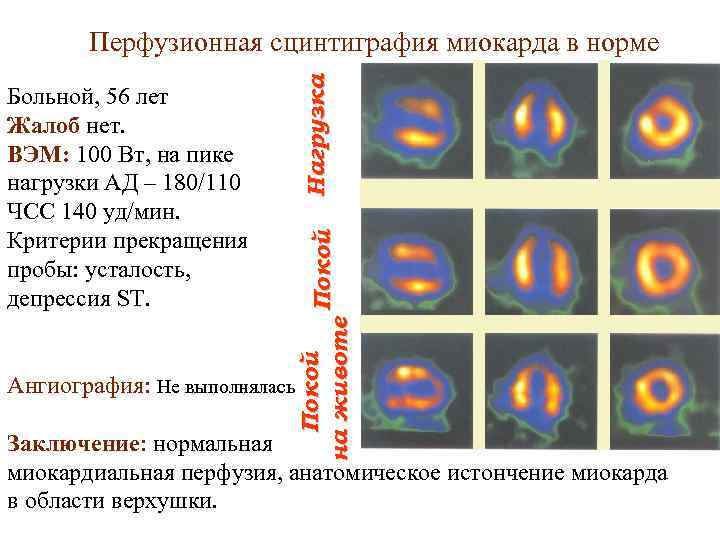

Ангиография: Не выполнялась Покой на животе Больной, 56 лет Жалоб нет. ВЭМ: 100 Вт, на пике нагрузки АД – 180/110 ЧСС 140 уд/мин. Критерии прекращения пробы: усталость, депрессия ST. Нагрузка Перфузионная сцинтиграфия миокарда в норме Заключение: нормальная миокардиальная перфузия, анатомическое истончение миокарда в области верхушки.

Ангиография: Не выполнялась Покой на животе Больной, 56 лет Жалоб нет. ВЭМ: 100 Вт, на пике нагрузки АД – 180/110 ЧСС 140 уд/мин. Критерии прекращения пробы: усталость, депрессия ST. Нагрузка Перфузионная сцинтиграфия миокарда в норме Заключение: нормальная миокардиальная перфузия, анатомическое истончение миокарда в области верхушки.